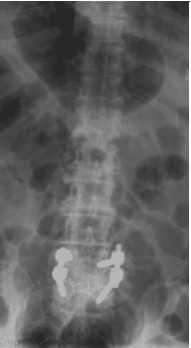

X-rays and MRI of the Lumbar spine showed L4-5 degenerative spondylolisthesis

and severe spinal stenosis.

Patient underwent decompression laminectomy with decompression of nerve roots and transforaminal interbody fusion using PEEK (polyether ether ketone) cage and pedicle screw and rod fixation for fusion at L4-5 level.